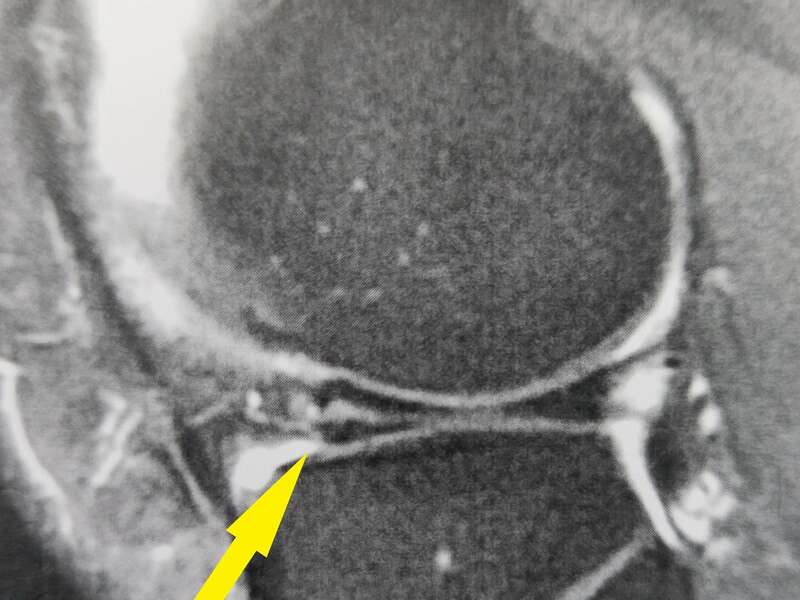

L’IRM (ou l’arthroscanner) confirme l’existence d’une lésion méniscale et sa localisation.

L’anse de seau méniscale est une fissure verticale qui s’étend de la corne postérieure à la corne antérieure. Cette anse est le plus souvent luxée dans l’échancrure inter-condylienne et provoque des blocages en extension.